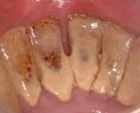

中等度歯周炎の症例です。歯ぐきが赤く腫れ、多量の歯石を認めます。力をかけると歯が動揺します。

細菌が歯槽骨まで侵入し、歯槽骨の破壊が起こっています。